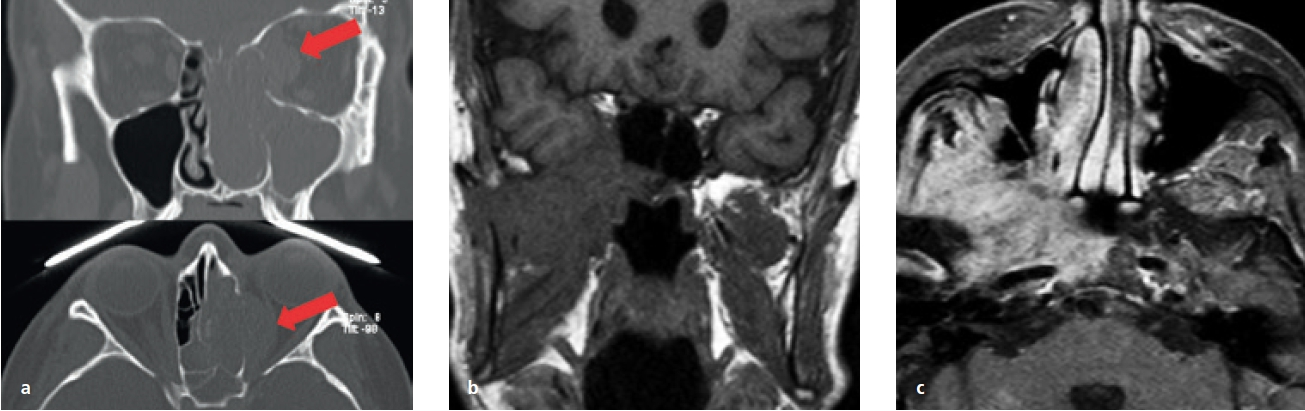

Von dieser Form der Pizerkrankung ist die allergische Pilzsinusitis (AFS, allergic fungal sinusitis) abzugrenzen [16]. Diese immunologische Erkrankung geht mit einer generalisierten NNH-Entzündung (Pansinusitis), Asthma und Polyposis einher (Abb. 12).

Eine Übersicht neoplastischer Formationen in der Kieferhöhle und auch in der unmittelbaren Umgebung ist in der Tabelle 3 zu sehen. In Bezug auf das Auftreten aller malignen Neubildungen sind sie vergleichsweise selten. Dennoch sind die malignen Erkrankungen der Kieferhöhle viel häufiger als die der anderen NNH [7,21–23). Im klinischen Alltag hat sich gezeigt, dass eine Früherkennung schwierig ist, da sich die Symptome nur wenig von der entzündlichen Symptomatik unterscheiden. Suspekt sind immer Formveränderungen der Kieferhöhlenwandungen und Okklusionsstörungen. Aber auch persistierende Schmerzen (Abb. 15a bis c) sollten als Warnsignal bewertet werden.